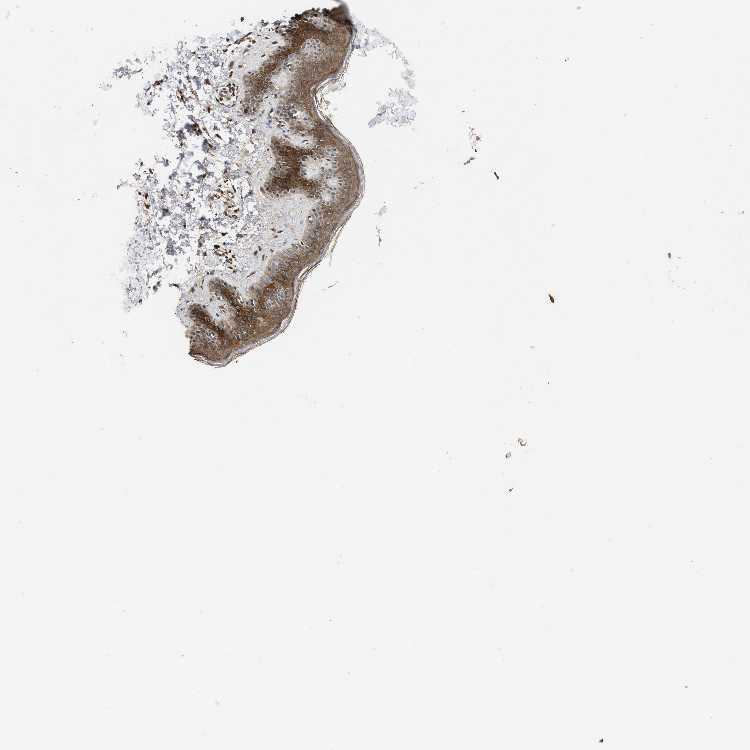

SKIN 1 - Antibody stainingi

Antibody staining in the annotated cell types in the current human tissue is reported as not detected, low, medium, or high, based on conventional immunohistochemistry profiling in selected tissues. This score is based on the combination of the staining intensity and fraction of stained cells.

Each image is clickable and will lead to virtual microscopy that enables deeper exploration of all samples and also displays staining intensity scores, fraction scores and subcellular localization as well as patient and tissue information for each sample.

Antibody HPA021297

Langerhans Medium

Fibroblasts Medium

Keratinocytes Medium

Melanocytes Medium